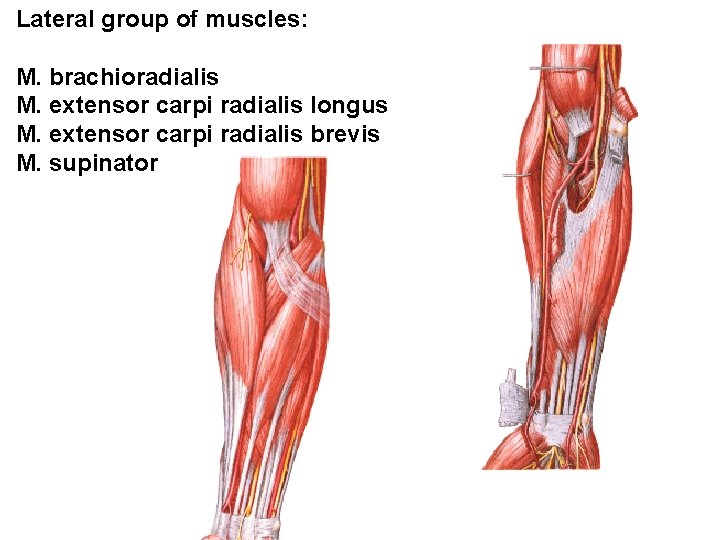

Lateral group of muscles: M. brachioradialis M. extensor carpi radialis longus M. extensor carpi radialis brevis M. supinator